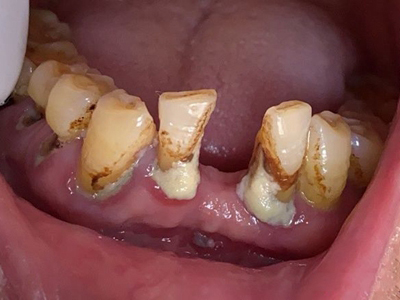

急性坏死性溃疡性龈炎起病急,病程短,常为数天至1-2周,以龈乳头和龈缘的坏死为其特征性损害,尤以下前牙多见,初起时龈乳头充血水肿,个别龈乳头顶端可发生坏死性溃疡,上覆有灰白色坏死物,中央凹下如火山口状。龈缘如虫蚀状,坏死区出现灰褐色假膜,擦去后可见出血创面。龈乳头被破坏后与龈缘成一直线,如刀切状。病损一般不波及附着龈,患处牙龈极易出血,疼痛明显并有腐败性口臭。